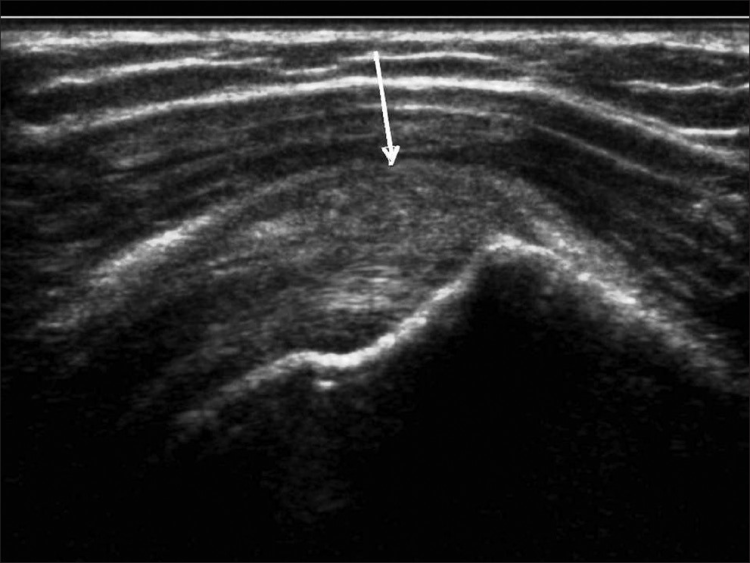

Los desgarros del manguito de los rotadores son la patología más común que se encuentra en los exámenes de ultrasonido del hombro.[7] La incidencia de lágrimas aumenta con la edad. Los desgarros de tendones se pueden clasificar de acuerdo con el grado de falla de la fibra, que van desde desgarros completos [Figura 7], desgarros de espesor total [Figuras 8, 9], desgarros de espesor parcial [Figuras 10-12] y desgarros intrasustancia [Figura 13 ]. Un desgarro agudo suele ir acompañado de derrame articular o bursal [Figura 12]. [7-9] La ausencia de derrame generalmente se relaciona con desgarros crónicos.[9] En un metanálisis sobre la precisión de la resonancia magnética, la artrografía por resonancia magnética y la ecografía en el diagnóstico de desgarros del manguito de los rotadores, la ecografía ofreció una alta sensibilidad y especificidad para la evaluación de los desgarros del manguito de los rotadores de espesor total (92,3 y 94,4 %, respectivamente) con 85,1 % y 92 %, respectivamente para todas las lágrimas.[7] El desgarro de espesor parcial aparece como un defecto o hendidura hipoecogénica en el tendón, afectando solo una parte de su espesor, mientras que un desgarro de espesor total se extiende desde la bolsa hasta la superficie articular del tendón. Un desgarro completo es un desgarro de espesor completo que afecta todo el ancho del tendón. El tendón se retrae medialmente, y la cantidad de retracción depende de la edad del desgarro. En las roturas crónicas, el tendón desaparece por debajo del arco coracoacromial, dejando la cabeza humeral descubierta por el supraespinoso, el denominado signo de la "cabeza desnuda". Los hallazgos de la ecografía incluyen la falta de visualización del tendón y la hernia del músculo deltoides. Los desgarros intrasustancia permanecen localizados en el tendón sin afectar sus márgenes. Los desgarros intrasustancia y de espesor parcial pueden ser difíciles de diferenciar de la tendinopatía focal.